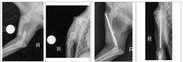

Schon bei seiner Ankunft hier, fiel uns auf, dass Pluto seinen rechten Vorderlauf nicht belasten konnte. Der Tierarzt bestätigte unsere schlimmste Befürchtung: Elle und Speiche sind vollständig gebrochen.

Bei genauerer Durchsicht der Unterlagen stellte sich heraus, dass es bereits Röntgenbilder vom Juni 2024 gibt – der Bruch bestand also schon seit über 14 Monaten. Pluto, geboren 2017, musste somit über ein Jahr mit einem unbehandelten Bruch leben. Ein kaum vorstellbares Leiden, das uns tief erschüttert, sprachlos und sehr traurig macht.

Wir haben ihn gleich nach seiner Ankunft ihn in einer Spezialklinik vorgestellt. Dort soll Pluto nun am Montag, den 15.09., um 08:30 Uhr operiert werden. Es handelt sich um eine schwierige Operation mit einem Kostenvoranschlag von 2.500 € – nur für den Eingriff selbst, ohne Nachbehandlung und bereits angefallene Untersuchungen.

Pluto wurde erfolgreich operiert. Ihm wurde keine Platte eingesetzt, sondern ein Gewindenagel.